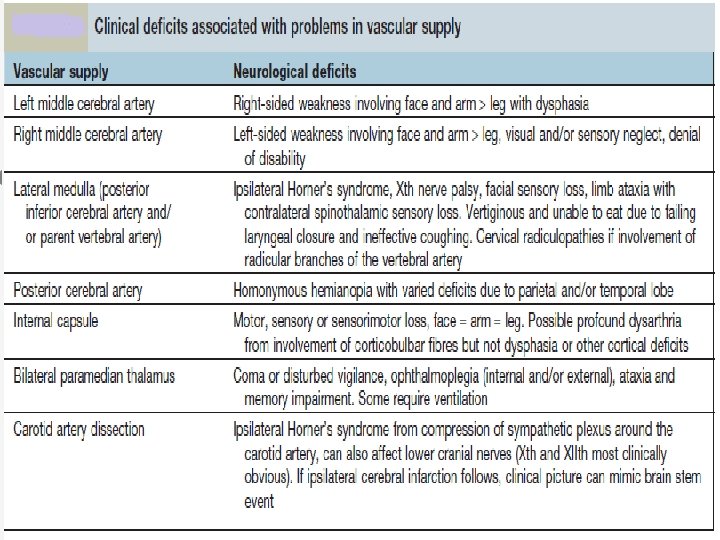

Types of Stroke Depending upon the blood supply of affected area of brain, stroke can be of following types: § ANTERIOR CIRCULATION STROKE: Carotid system § POSTERIOR CIRCULATION STROKE: Vertebrobasilar system

Localization of Lesion Midbrain: CROSSED HEMIPLEGIA: Ø 3 rd /4 th CN are involved on one side and hemiplegia of opposite side Pons: Ø 5 th, 6 th, 7 th and 8 th CN nuclei are present in pons. Ø One or more of these CNs are paralyzed on one side and hemiplegia is on the other side. Ø Pupils are pinpoint but reactive to light Ø Hyperpyrexia may be present Medulla Oblongata: Ø 9 th, 10 th, 11 th and 12 th CN nuclei are present in medulla. Ø One or more of these CNs are paralyzed on one side and hemiplegia is on the other side.

MIDDLE CEREBRAL ARTERY • Supplies lateral surface of frontal, perital and temporal lobes • Most of the motor and sensory cortex Ecxept the part on medial side and control lower limb, internal capsule Total Occlusion: • Uncrossed hemiplegia • Hemianesthesia • Global Dysphasia • Homonymous hemianopia • Apraxia, Agnosia Partial occlusion: • Any of the above features. • Lower limb is either not or minimally involved

ANTERIOR CEREBRAL ARTERY • Supplies MEDIAL surface of hemisphere • Motor and sensory cortex on medial side which control lower limb • Soon its origin it gives a penetrating branch (Heubner’s artery) which supply internal capsule (containing fibers of upper limb and face) Occlusion at the origin: Features are similar to total occlusion of MCB Occlusion of Heubner’s artery : • Weakness of upper limb and face Occlusion after the origin of Heubner’s artery : • Weakness of lower limb • Loss of cortical sensory function in lower limb

POSTERIOR CEREBRAL ARTERY • Branch of Basilar artery • Supplies occipital lobe which include visual cortex Occlusion: • • Visual field loss Homonymous hemianopia Visual agnosia Disorders of reading Disorders of color vision Memory impairment Motor dysfunction

LATERAL MEDULLARY SYNDROME • Also called posterior inferior cerebellar artery (PICA) thrombosis and Wallenberg’s syndrome) • Acommon example of brainstem infarction presenting as acute vertigo with cerebellar and other signs. It follows • Thromboembolism in the PICA or its branches, vertebral artery thromboembolism or dissection. • Features depend on the precise structures damaged. MEDIAL MEDULLARY SYNDROME • Characterized by a set of clinical features resulting from occlusion of the anterior spinal artery. This results in the infarction of medial part of the medulla oblongata.